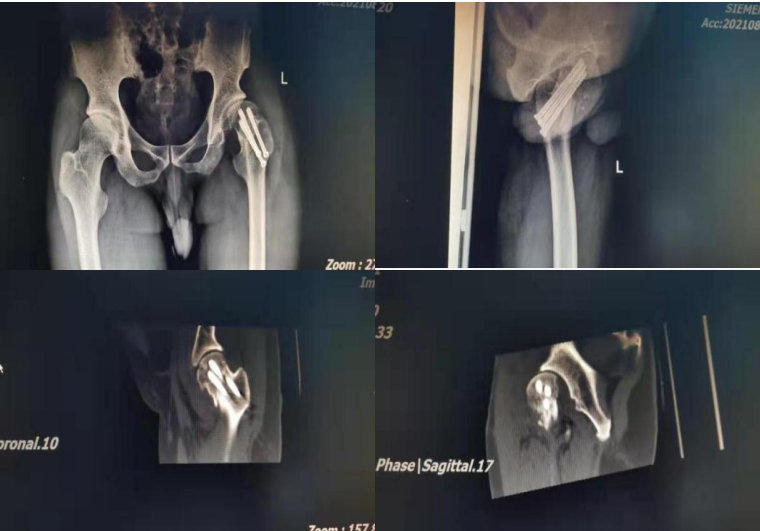

在征得患者及家屬同意后,陳定家團(tuán)隊(duì)決定為小吳實(shí)施“天璣骨科機(jī)器人輔助下行左股骨頸骨折空心釘固定術(shù)”,術(shù)中三維X線成像透視見到患者股骨頸頭下型骨折,切開骨折端解剖復(fù)位后,在天璣骨科機(jī)器人精準(zhǔn)“導(dǎo)航”下依次植入三枚空心釘,告別了傳統(tǒng)手術(shù)“暗箱操作”的局面。

術(shù)后